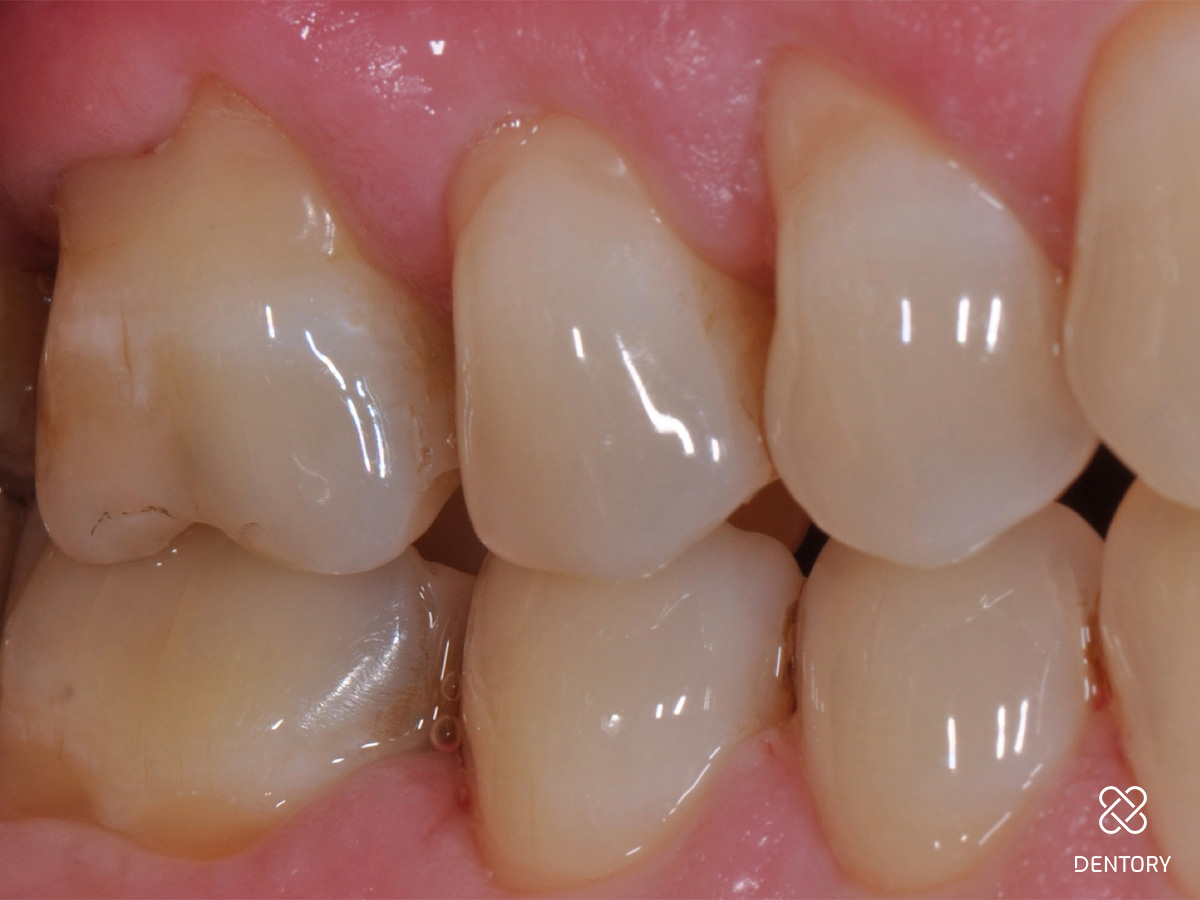

Abbildung 16

Die klinische Situation regio 16/17 sechs Monate nach Eingriff zeigt ein gesunde und stabile Gingivaverhältnisse.